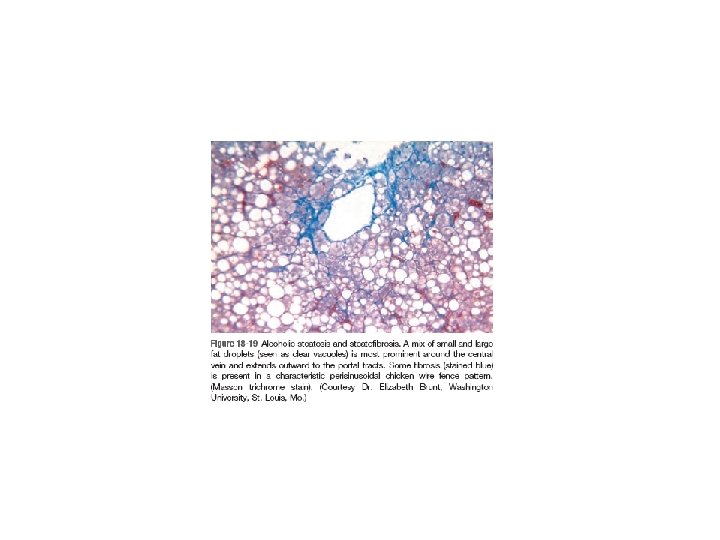

Alcoholic Liver Disease • Excessive alcohol (ethanol) consumption is the leading cause of liver disease in most Western countries. • There are three distinctive, albeit overlapping forms of alcoholic liver injury: (1) hepatocellular steatosis or fatty change, (2) Alcoholic (or steato-) hepatitis, (3) Steatofibrosis including cirrhosis in the late stages of disease.

• Alcoholic steatofibrosis: Alcoholic hepatitis is often accompanied by prominent activation of sinusoidal stellate cells and portal fibroblasts, giving rise to fibrosis. Early stages of scarring can regress with cessation of alcohol use, but the farther along toward cirrhosis the liver gets, the more vascular derangements prevent a full restoration of normal. Complete regression of alcoholic cirrhosis, while reported, is rare